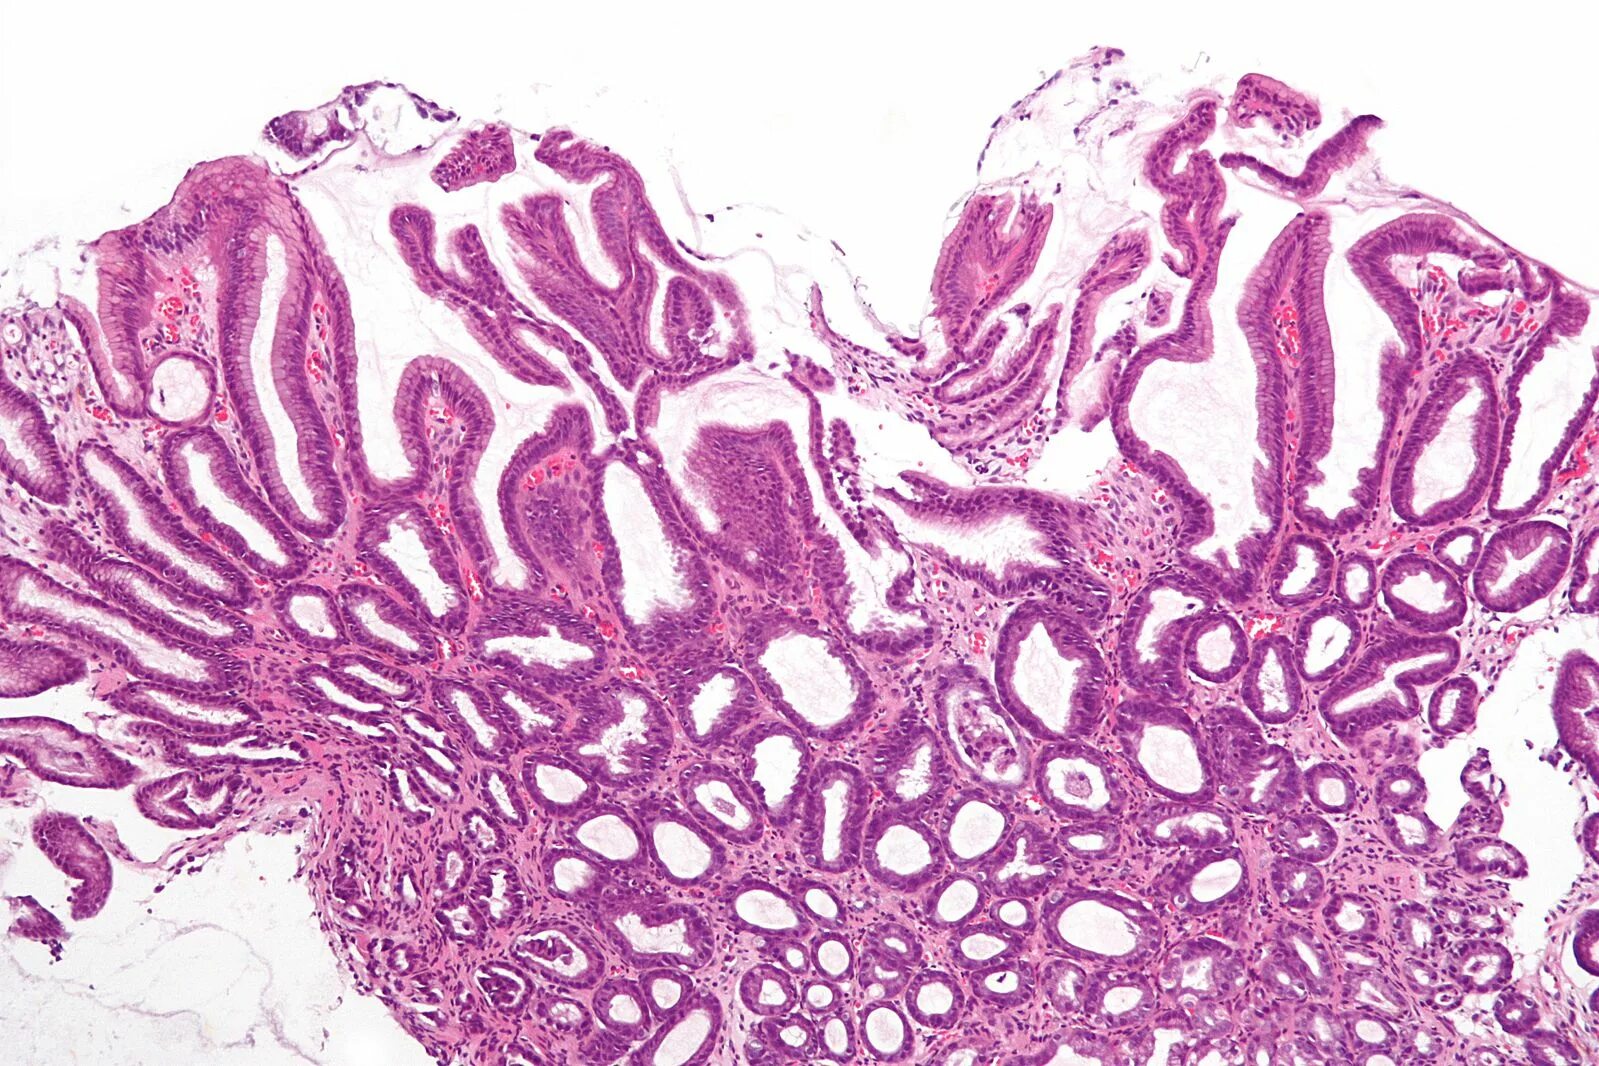

Гистологические заболевания